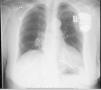

Después de 36h de la intervención la paciente presenta diaforesis; se realiza radiografía de tórax sugiriendo que el electrodo ventricular del cardiodesfibrilador implantable (CDI) se encontraba fuera del corazón (figs. 1 y 2); minutos después la paciente presenta palidez, frialdad generalizada con taquicardia e hipotensión severa; al examen físico se obtiene TA: 64/30mmHg; FC: 120lpm; FR: 30rpm, SatO2: 91%, ruidos cardiacos velados y ecocardiograma el cual muestra colapso ventricular derecho, derrame pericárdico y el electrodo (figs. 3 y 4), por lo que es trasladada inmediatamente a salas de cirugía con la sospecha de taponamiento cardiaco; se realiza esternotomía media evidenciando: hemopericardio aproximadamente 2.000cc, soluciones de continuidad en número de 2 en el ventrículo derecho, la primera puntiforme de 4mm, correspondiendo al electrodo de fijación auricular el cual se movilizó muy probablemente durante el preoperatorio, dado que en la radiografía prequirúrgica se encontraba normoinserto, y otra de 3cm en la pared anterior del ventrículo derecho a través de las cuales emergen los electrodos de fijación activa del dispositivo (fig. 5), con sangrado activo masivo, aurículas, ventrículos y grandes vasos colapsados; se introduce sonda Foley sobre defecto de mayor tamaño con posterior insuflación de la misma controlando parcialmente el sangrado, cardiorrafia y paso de hemoderivados directo al corazón por la sonda; presenta asistolia requiriendo maniobras de reanimación cardiocerebropulmonar avanzadas durante 20min sin obtener respuesta, por lo que la paciente fallece.

El implante de estos dispositivos se rige por protocolos estrictos y técnicas que buscan disminuir complicaciones y optimizar su funcionalidad, teniendo como principio el de alojar a nivel auricular y/o ventricular electrodos según sea la patología. En la figura 7 observamos una radiografía de tórax con posicionamiento adecuado de los electrodos a nivel de la aurícula y ventrículo derechos, sin embargo, si correlacionamos esta imagen con la de nuestro caso la diferencia en cuanto al electrodo ventricular derecho no es muy significativa, lo cual le confiere la complejidad a este tipo de complicaciones y nos conduce a la realización de otro estudio imagenológico en el paciente que se encuentra estable7.

Radiografía de tórax anteroposterior (A)-lateral (B). Adecuado posicionamiento de los electrodos en la aurícula y ventrículo derechos7.

El diagnóstico de la perforación ventricular secundaria a electrodos de marcapasos la podemos identificar y confirmar con radiografía de tórax como lo observamos en nuestro caso, en el cual se encontraba el electrodo ventricular fuera de la cámara cardiaca. Otros métodos diagnósticos pueden ser el fluoroscopio, la ecocardiografía o TAC de tórax, encontrándose en esta última alteraciones de hasta el 15% de pacientes asintomáticos durante los controles postimplante del dispositivo10,23,24. En el ecocardiograma tridimensional podemos obtener una mayor precisión que en la TAC de tórax en la identificación de la perforación ventricular por electrodos, debido principalmente al efecto tomográfico conocido como «estrella» causado por los materiales del electrodo (figs. 8 y 9), haciendo difícil el diagnóstico. No existe consenso sobre criterios radiográficos diagnósticos universalmente aceptados entre los grupos de radiólogos, por esto la correlación clínica nos orienta. Todos estos estudios orientan al diagnóstico, pero la no evidencia del electrodo fuera del corazón no nos descarta la complicación, como sucedió en nuestro caso donde hubo una migración del electrodo de fijación activa auricular derecho con posterior perforación del ventrículo ipsilateral, lo cual nos muestra una complicación aún más infrecuente debido a la perforación ventricular por el electrodo ubicado en la aurícula17,25,26.